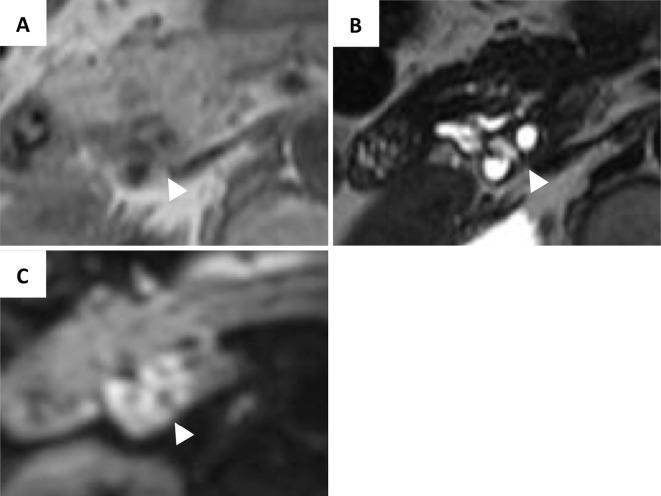

A small proportion of intraductal papillary mucinous neoplasms (IPMNs) are accompanied by type 1 autoimmune pancreatitis (AIP); however their clinical courses and image characteristics have not been fully reported. A 65-year-old woman was referred to our hospital for the examination of a pancreatic head cyst that had shown exacerbation for two years. Several images demonstrated a multilocular cyst with a symmetrically thickened, enhanced, cyst wall. Cancerization of IPMN was suspected, and pancreatoduodenectomy was performed. The resected specimens showed a multilocular cyst with solid areas. The solid areas demonstrated pathological findings that corresponded with type 1 AIP. Papillary epithelia suggestive of IPMN was recognized in some parts of the cystic wall.

一小部分导管内乳头状黏液性肿瘤(IPMN)伴有1型自身免疫性胰腺炎(AIP);然而,它们的临床病程和影像特征尚未得到充分报道。一名65岁女性因胰头囊肿检查被转诊至我院,该囊肿已加重两年。多项影像显示为多房囊肿,囊壁对称增厚、强化。怀疑IPMN癌变,遂行胰十二指肠切除术。切除标本显示为带有实性区域的多房囊肿。实性区域显示出与1型AIP相符的病理结果。在囊壁的某些部位可识别出提示IPMN的乳头状上皮。